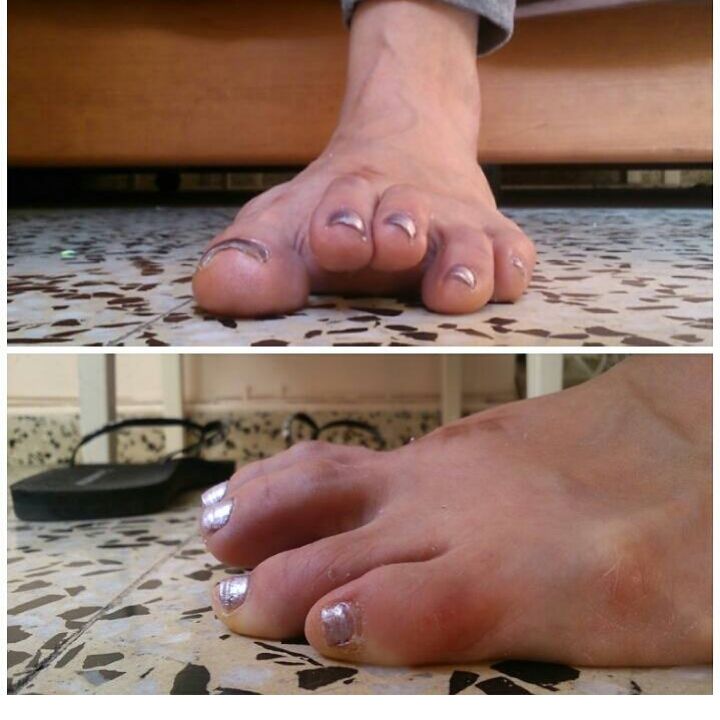

El año pasado volví a llevarlos y esta vez le hizo más gracia la propuesta y acordamos que correríamos los tres la del 2016, que estarán conmigo. Yo para entonces estaba recién intervenida de mi segunda operación de pies: Osteotomía de Weill en segundo y tercer metatarsiano de ambos pies y fijación con cuatro tornillos de titanio. Yo todavía iba coja y no podía ni imaginar que mis operaciones habían sido un absoluto fracaso, quedando peor de lo que estaba, con más dolor y, además, rigidez en los cuatro dedos intervenidos, que me provocan dolor y dificultad de equilibrio, amén de una estética propia de un orco de Mordor.

El año pasado volví a llevarlos y esta vez le hizo más gracia la propuesta y acordamos que correríamos los tres la del 2016, que estarán conmigo. Yo para entonces estaba recién intervenida de mi segunda operación de pies: Osteotomía de Weill en segundo y tercer metatarsiano de ambos pies y fijación con cuatro tornillos de titanio. Yo todavía iba coja y no podía ni imaginar que mis operaciones habían sido un absoluto fracaso, quedando peor de lo que estaba, con más dolor y, además, rigidez en los cuatro dedos intervenidos, que me provocan dolor y dificultad de equilibrio, amén de una estética propia de un orco de Mordor.Hace un par de meses conocí a una persona que salió de mi vida tal y como había entrado. Pero antes de irse, me hizo un regalo: Esta persona, con una hernia discal en el mismo espacio intervertebral que la mía, me contó que se inició en el running por su cuenta, pesando 17 kilos más que en la actualidad. Comenzó corriendo un minuto al día y en dieciocho meses de práctica diaria es capaz de correr una hora y media y mantener una conversación al mismo tiempo. Me aseguraba «A mí al principio también me dolía la hernia, ¡me dolía todo! Pero luego fue como si el cuerpo se acostumbrase». He querido explicaros que esta persona pasó de largo por mi vida porque creo que todas las personas que se cruzan en nuestra vida, lo hacen por una razón. Y quizá esta persona pasó por la mía sólo para decirme justo lo que yo necesitaba oír.

A la lucha mental, se une el esfuerzo físico, porque os aseguro que mover un cuerpo con tanto sobrepeso no es fácil, y el dolor de pies, ya que corro con zapatillas de doble amortiguación talón/metatarso, plantilla completa de gel de 5 mm de espesor y una planilla que me hizo el podólogo con barra para elevar la cabeza metatarsal. Y aún con todo eso junto, tengo dolor, y algún día me tengo que tomar antiinflamatorios para soportarlo.